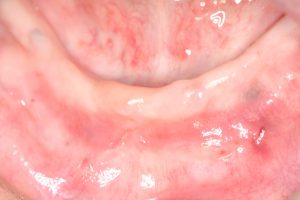

| 初診時:上の歯のすべてが虫歯が進行しすぎて

残せる状態ではありませんでした |

下の歯はすでに1本もない状態でした 正面から見た状態です |